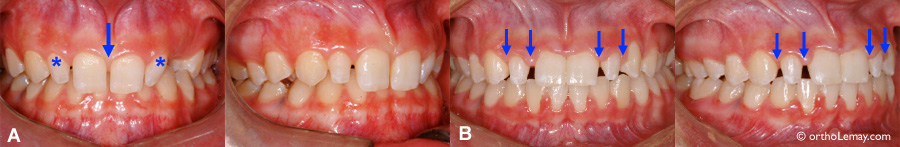

Tous ces cas ont une absence héréditaire des 2 latérales supérieures ce qui permet aux dents adjacentes de se déplacer et de créer ainsi des espaces interdentaires. Parfois, il ne manque qu’une seule latérale et l’autre latérale présente est souvent de dimension réduite (étroite).

Les dents étroites, souvent des latérales supérieures, sont une des causes principales d’espaces interdentaires affectant les incisives supérieures. Pour optimiser la fonction et l’esthétique, il est préférable de corriger la malposition des dents avant de les faire élargir de façon “définitive”.

• (A) Dentition avec 2 latérales étroites (“grain de riz”) avant le traitement.

• (B) Après les corrections, les espaces sont distribués de façon optimale pour permettre d’élargir les latérales. Les autres aspects e la malocclusion ont aussi été corrigés.